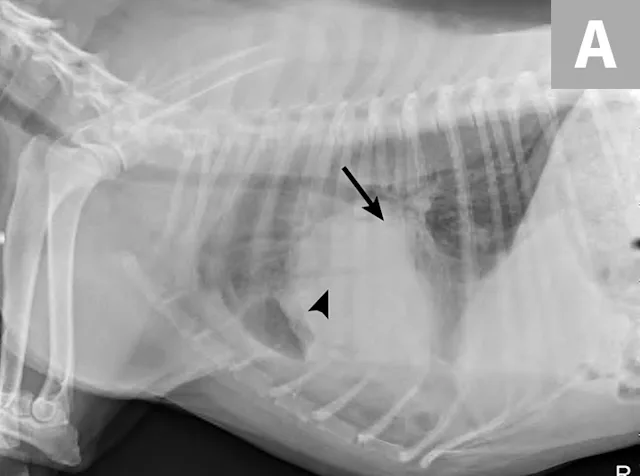

Radiographs obtained after thoracocentesis demonstrated improved pleural effusion and consolidation of the left middle lung lobe (Figure 3). Based on the soft tissue bulge near the hilum and the air bronchocram extending cranially, the primary differential was lung lobe torsion (LLT). Other considerations included pulmonary mass, abscess, or granuloma.

FIGURE 3A

Right lateral (A) and ventrodorsal (B) thoracic radiographs obtained after thoracocentesis showing improvement in pleural effusion with a persistent soft tissue opacity in the left mid-to-cranial thorax. An air bronchogram is seen extending cranially from the hilus (arrowhead) where a subtle bulge (arrow) is present.